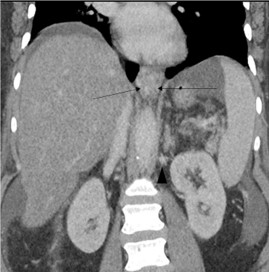

On hospital day ten, she developed acute dyspnea and hypoxia requiring supplemental O2. The hemoglobin was 6.2 g/ dL, declined from 8.6 g/dL 24 hours earlier. The patient had no hematemesis, melena, or hematochezia. CT pulmonary angiogram demonstrated a large right pleural effusion (Figure 2) and a new 9.5 × 3.6 × 5.0 cm large heterogeneous hyperdense lesion in the lower posterior mediastinum abutting the esophagus consistent with a mediastinal hematoma. No pneumomediastinum was seen to indicate an esophageal rupture. Diagnostic thoracentesis confirmed hemothorax with return of frank blood. The patient was subsequently intubated and transferred to the intensive care unit, where she was placed on vasopressors and initiated on massive transfusion protocol for hemorrhagic shock. No bloody output was noted from her orogastric tube or her rectum. Repeat CT angiogram six hours later revealed interval enlargement in the mediastinal hematoma to 10 × 7.4 × 3.8 cm and dependent higher density fluid suggesting blood in the right pleural effusion. Extensive posterior mediastinal paraesophageal varices were demonstrated but no active extravasation was noted.

Figure 2: CTA chest on hospital day 10: Coronal images showing new hyperdense paraesophageal mass consistent with hematoma (black arrows). Esophagus marked with white arrows. Also seen is new large pleural effusion.